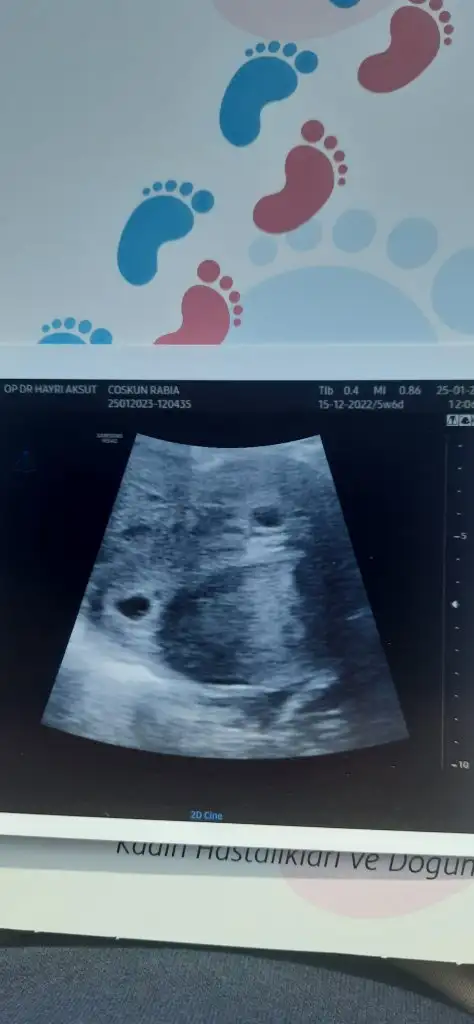

Merhaba arkadaşlar 1 ay öncesine kadar benim de takip ettiğim bir başlıklı burası, 26 aralıkta biri 19 mm biri 20 mm olmak üzere 2 yumurtam büyümüştü ve çatlatma iğnesi vurmuştu doktorum akabinde de 28 aralıkta aşılamam yapıldı. Aşılamadan sonraki 11. Günde test yaptım ve silik çift çizgi gördüm hemen kan verdim ve kan değerim 51 çıktı. O günden bu güne kadar kan takibi yaptım ve bugün ilk doktor randevum vardı. Bugün ikiz olduğunu öğrendik ilk defa ve şok olduk. Herkes genelde ilk aşılama tutmaz der moralinizi bozar ama sakın hiçbir şey için moralinizi bozmayın kızlar. Rabbim ol diyince her şey oluyor ve Allahım isteyen kimsenin kucağını evlatsız bırakmasın. Ben 27 yaşındayım elimde hiçbir sorun yoktu bende pcos vardı ve 1.5 yıl hamile kalmamıştım normal olarak o yüzden direkt aşılama ile başladık ve çok şükür ilk aşılamamızda ikizlerimize hamile kaldım 😇

• 20230125_115429.webp

20230125_115429.webp

16,9 KB · Görüntüleme: 68